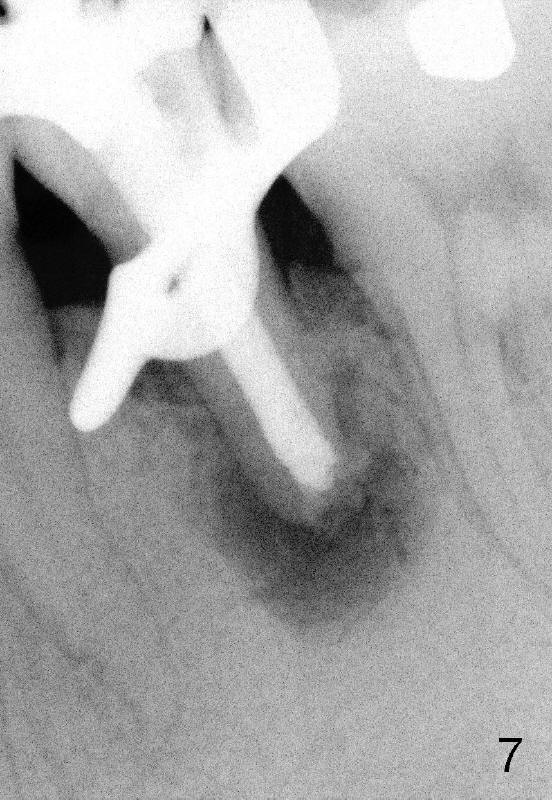

A 40-year-old Chinese man has periodic (once a month) mild pain and swelling in the lower left quadrant. Clinical exam reveals dens evaginatus (Fgi.1': <) in #20. Upon pressure from mouth mirror handle, there is limited amount of purulent discharge from the fistula (Fig.1": <). Preop PA shows a large canal with large periapical radiolucency (Fig.1). RCT started on Aug 6, 2010 with #70 file at 20 mm (Fig.2), #120 file at 16 mm (Fig.3) and CaOH paste in the canal (Fig.4). The dressing changed on Oct 8, 2010 (Fig.5). RCT finished on Jan 25, 2011 with master cone (rolled with several gutta perchae) (Fig.6), lateral condensation (Fig.7) and after vertical condensation and build-up (Fig.8). The canal was wet in the last two appointments with no sign of apexification. Follow up is done in 7 months (Fig.9), 11 months (Fig.10) and 18 months. Although the patient reports no pain after the treatment, the fistula remains with purulent discharge. The patient does not accept apical surgery. What should we do? Retreat with MTA (1,2,3)?